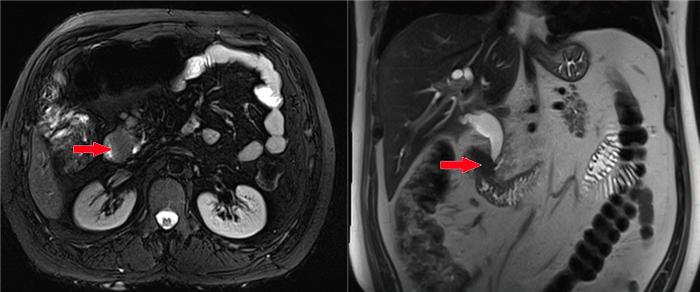

经过与患者详细沟通,医生为患者进行了CT、MRCP、胃镜等相关检查,以明确患病原因、病灶位置等情况。经相关检查及医生诊断,患者被诊断为十二指肠肿瘤,而且肿瘤已经侵犯到胰头。

MRCP(磁共振胰胆管造影)检查